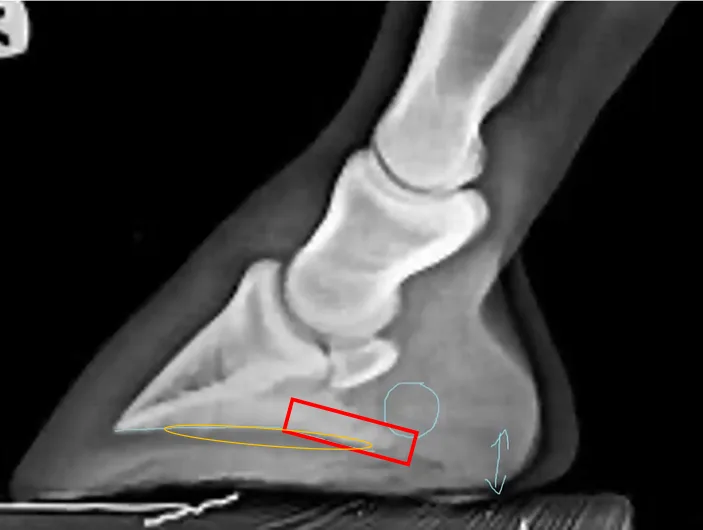

James suggests that the traditional measurement of palmar angle, which follows the solar border of P3 (B)(Figure 11), can become inaccurate due to bone remodelling (Figure 12). He suggests instead the use of a measure starting at the volar arch of P3, terminating at the lower aspect of the lower palmar process.

Figure 12. Credit Matt James. Showing the discrepancy between the A and B measurements. Bone remodelling has created two angles to the solar surface of P3.

Measurement A and B become distinctly different in this image, while B would be significantly negative, A would be more toward neutral or even slightly positive. James suggests trigonometry using the length of the frog and height of the lateral sulcus gives the angle of A (Figure 13).

First and foremost, we need to establish the clinical relevance of angle A. Is this the angle we should be using? James suggests that bone remodelling in this context is proliferative (Figure 14).

Figure 14. Credit Matt James. James’ theory suggests the area in red is new bone growth due to loading over time leading the study to suggest that PA should be taken as measurement A.

To establish the clinical relevance of measurement A and whether it should be used over measurement B, we must understand whether the red area is proliferated bone or if the orange area has been reabsorbed. It is widely understood that long periods of increased load on the distal phalanx results in osteolysis. Without historical radiographs of this horse, it becomes unclear as to whether measurement A versus measurement B is actually an indication of the amount of bone loss in the orange area. This becomes a fundamental question regarding the clinical relevance of measurement A, it is only the more correct measurement if the red area is proliferation! If it is in fact the case that the orange area has been resorbed, then measurement A becomes a Fallacy. Whether the trigonometry works becomes clinically irrelevant in the context of negative palmar angles. Whether it holds relevance in other contexts is to be researched.